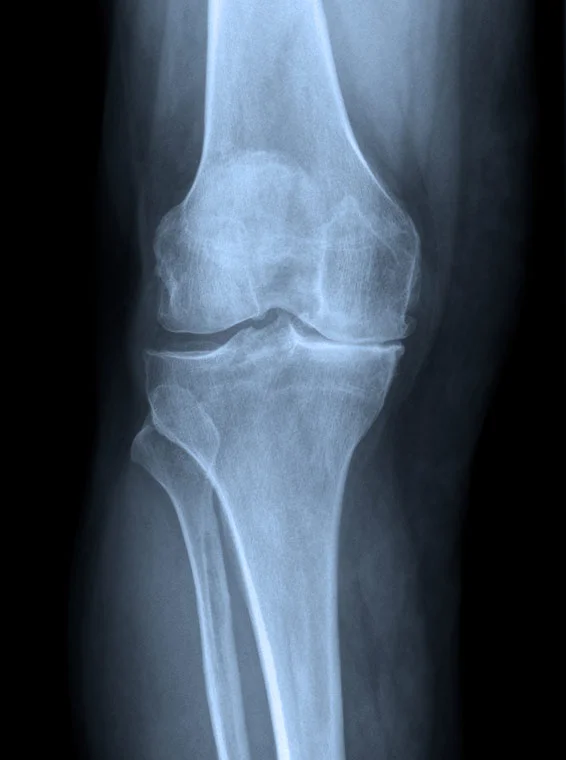

Knee replacement surgery, which is essentially resurfacing of the articular surfaces of the joint and reducing inflammation and therefore pain in the knee, has a high success rate in relieving symptoms. Approximately ninety-five out of every hundred joint replacement procedures give good pain relief for a prolonged period of time following the surgery. Knee replacement procedures have become more common due to the aging population.

• In those patients where there is arthritis throughout the knee which is severe, a full knee replacement will be recommended.

• In those patients with only limited arthritis in one part of the knee, the partial knee replacement procedure may be possible. The advantages of a partial knee replacement are that the procedure is a smaller operation with faster recovery time.